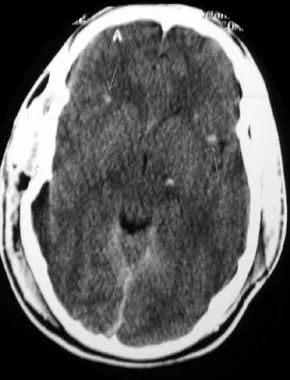

- CT findings suggestive of DAI

- CT-findings in DAI

- Blurring of the grey- and white-matter junction

- Punctate hemorrhages

- Cerebral edema